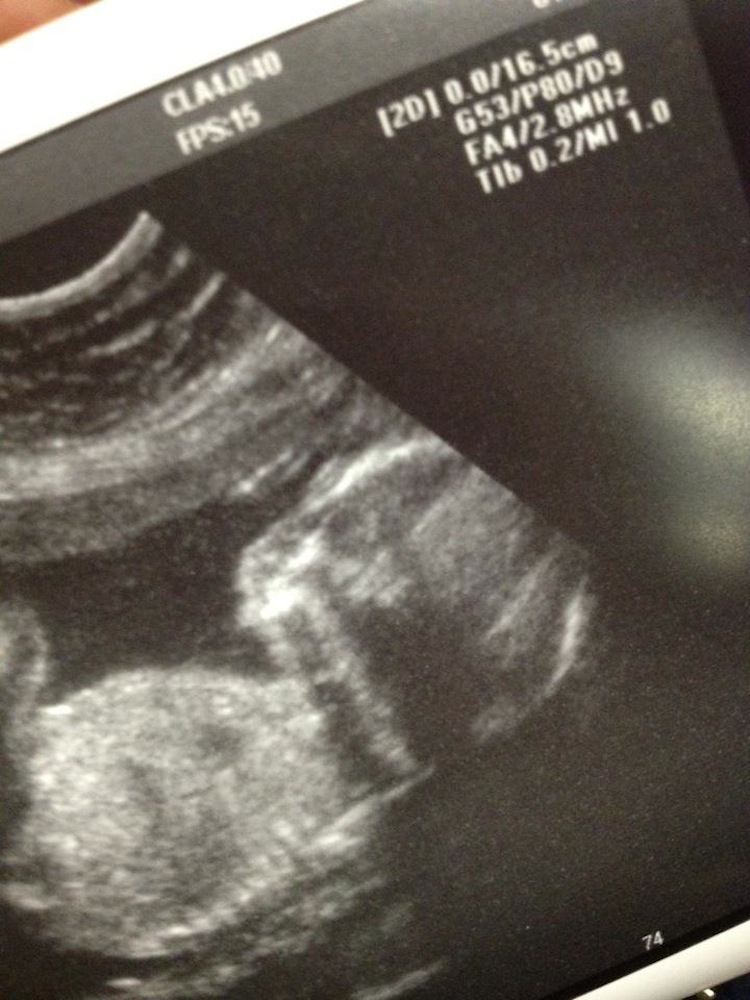

I love that we got such a great view of his face. I told Josh that my favorite part is how his little lips are parted and he looks kind of sleepy-smiley.

We got such great views of him during the ultrasound. He was very wiggly and funny. At one point, he put both of his hands over his face, like, "Go away, guys!"

*21 weeks, 1 day in this photo. Measuring 21 weeks, 5 days.